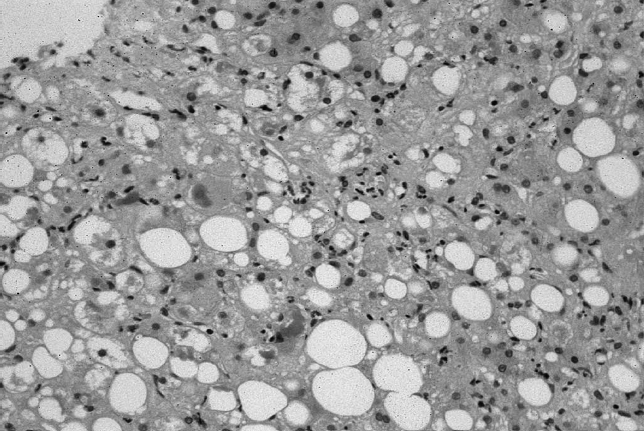

Во всех полях зрения гепатоциты находились в состоянии разной степени выраженности жировой дистрофии (от микровезикулярного до макровезикулярного стеатоза), лишь в отдельных исследуемых случаях жировая дистрофия гепатоцитов носила очаговый характер. Как правило, мелкие жировые капли отмечались в цитоплазме гепатоцитов, располагающихся преимущественно в центре печеночных долек (центролобулярно), тогда как крупные жировые вакуоли были визуализированы в гепатоцитах периферических частей долек. В срединных и периферических отделах печеночных долек среди гепатоцитов с «пенистой» жировой дегенерацией цитоплазмы определялись гепатоциты в состоянии крупнокапельной жировой дистрофии со смещением ядра к клеточной оболочке с образованием так называемых «перстневидных клеток» (рис. 1).

Рис. 1. Макровезикулярный стеатоз (окраска гематоксилином и эозином, ув. ×400)